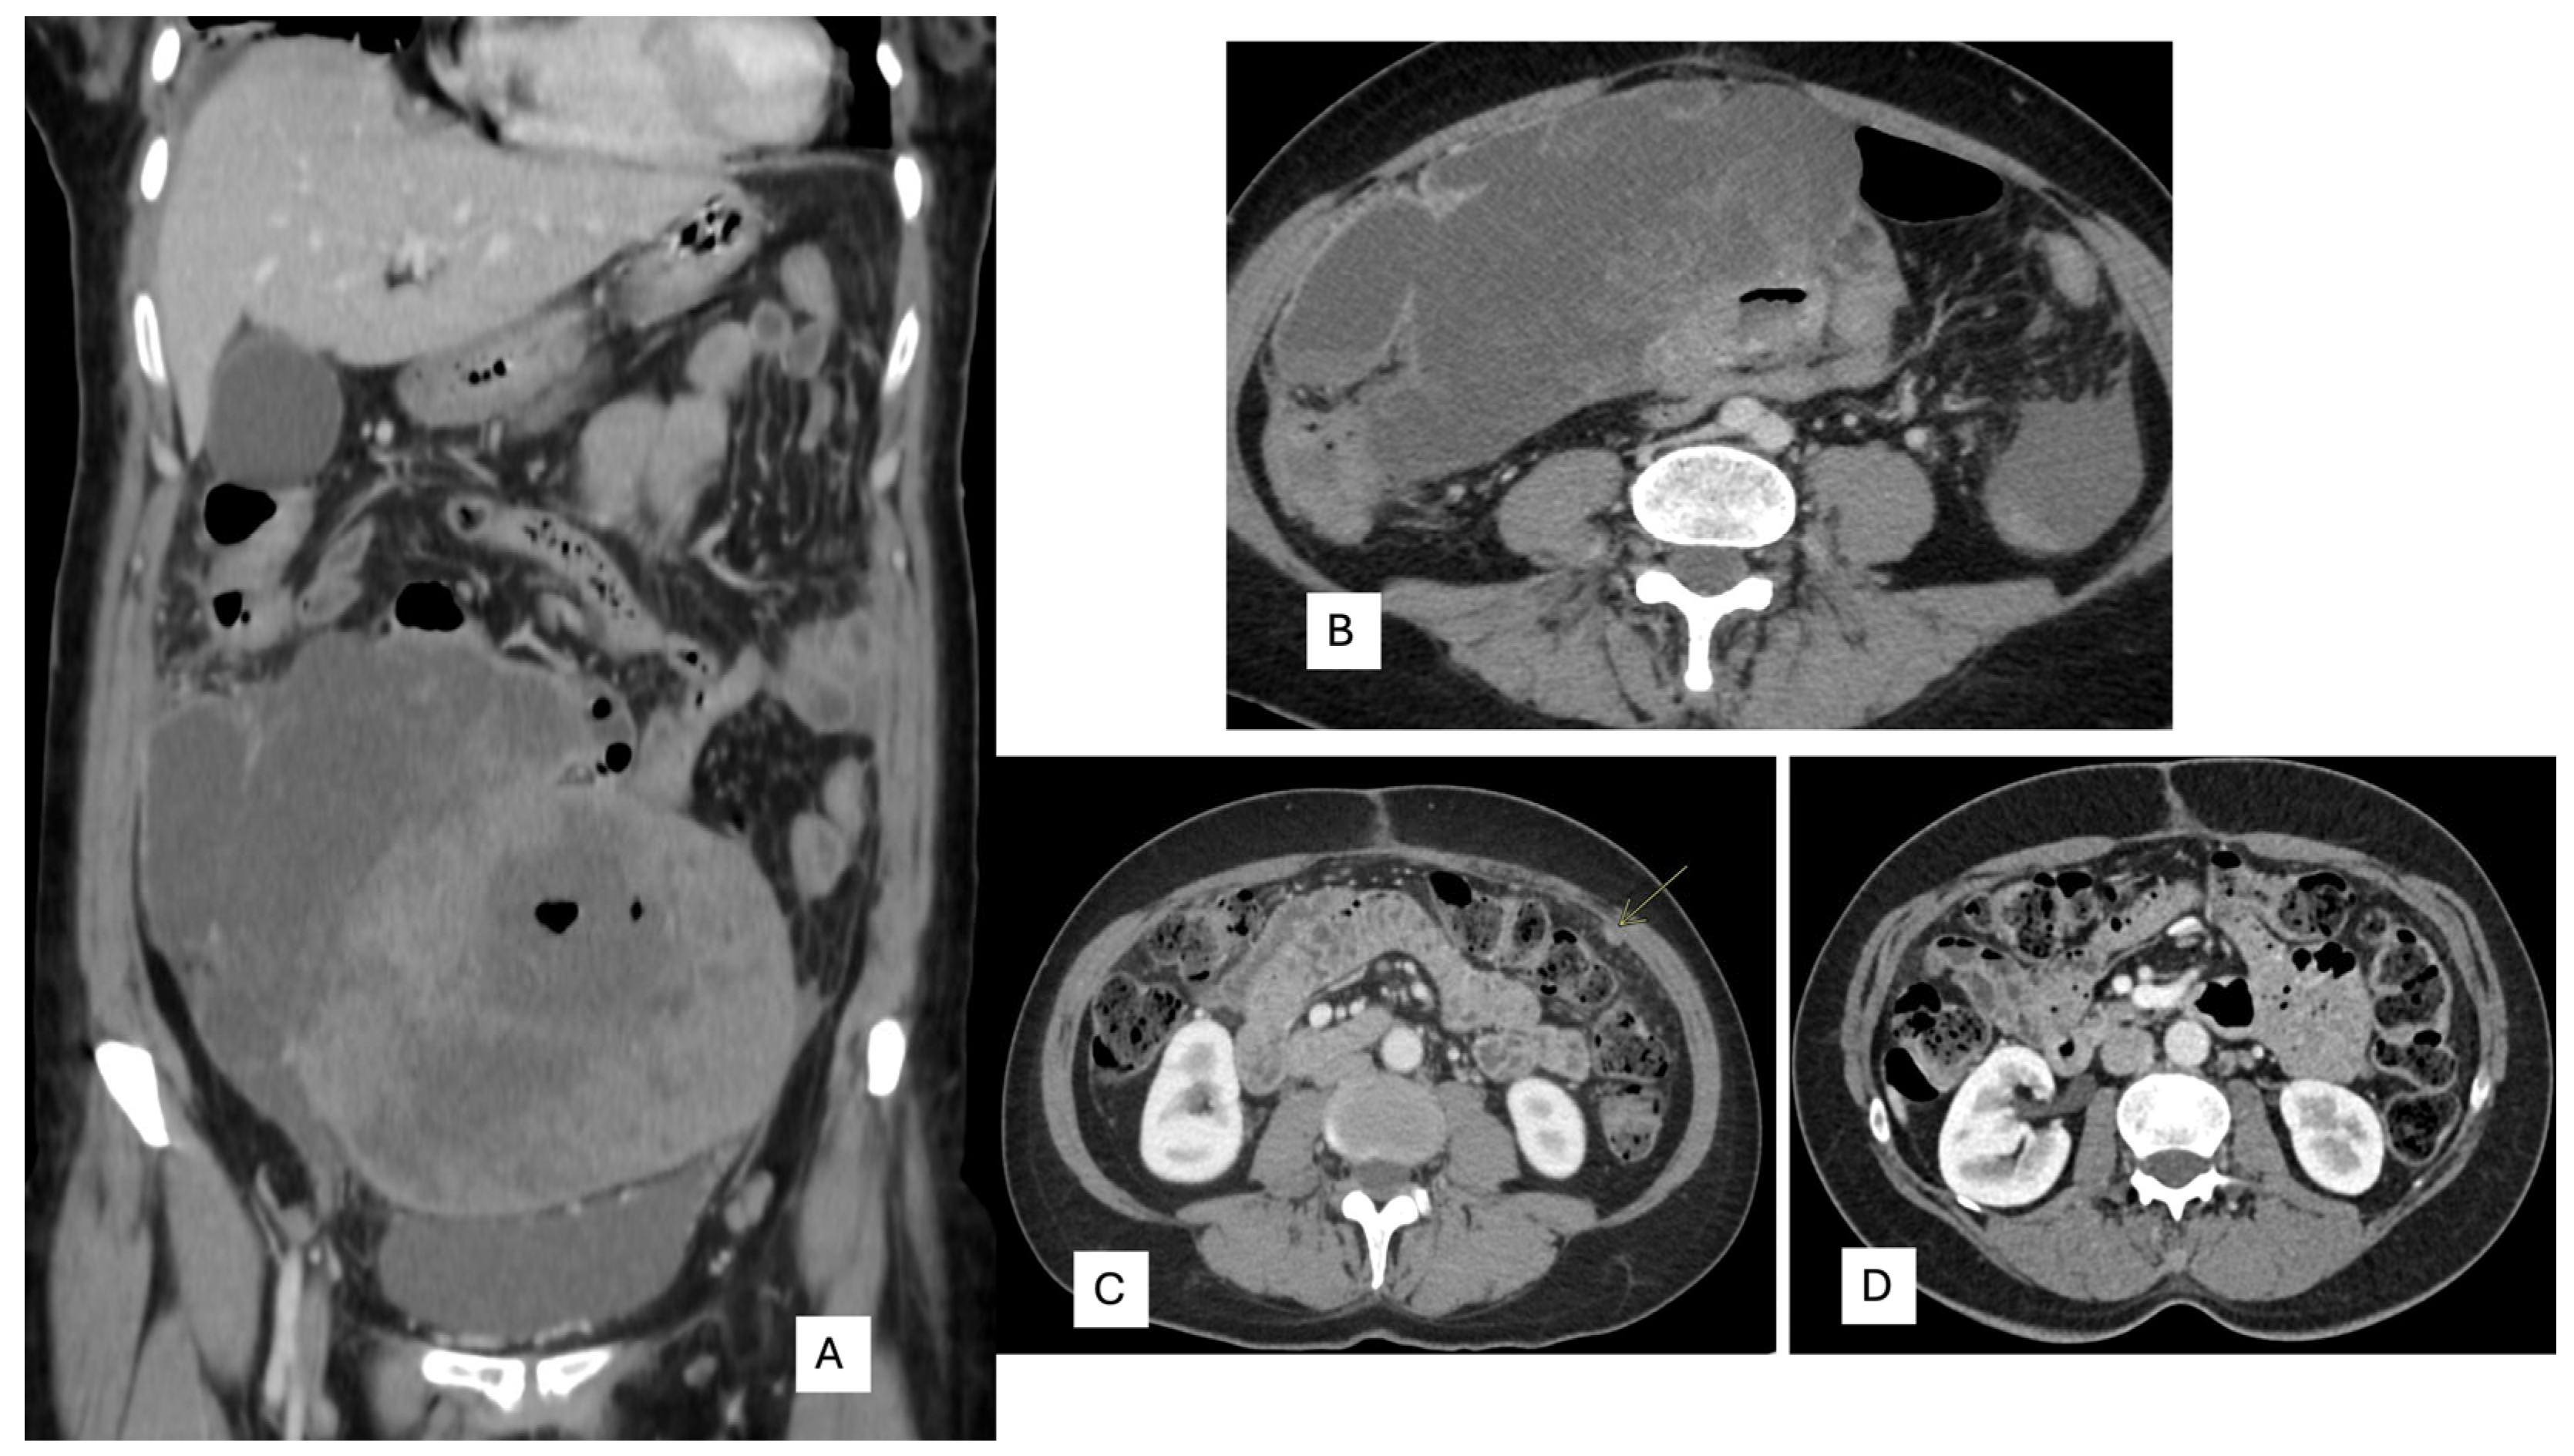

| Present case | 57/F | Pelvic/27 cm | Spindle | 20 | high | TILs and lymphoid nodules | DOG1+++.CD117:++ CD34:+, SDHB: retained PanTRK:+ focal | NTRK3::ETV6 | NTRK3 positive | Surgery and Entrectinib | Yes/1 | Alive/3 |